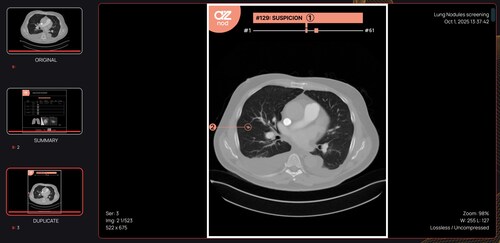

AZmed Expands Into CT Imaging With CE-Marked AZnod, An AI Tool for Lung Nodule Detection and the First Product in the Rayscan® Line

PARIS, Dec. 15, 2025 /PRNewswire/ -- AZmed, one of the leading companies in artificial intelligence (AI) for radiology, announced today the CE marking of AZnod, its first AI tool for computed tomography (CT) within the new Rayscan® product line. This expansion complements AZmed's existing Rayvolve® AI Suite, extending the company's portfolio beyond standard X-rays to include advanced CT-based analysis.

AZnod is designed to aid lung cancer screening programs by providing standardized detection and comprehensive characterization of pulmonary nodules on CT scans.